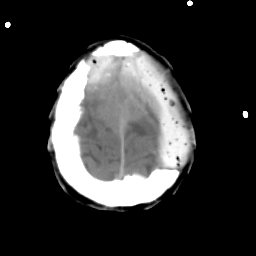

Meningioma: Roentgen-ray CT #2 -- Slice #19

[Home][Help][Clinical] Slice 19